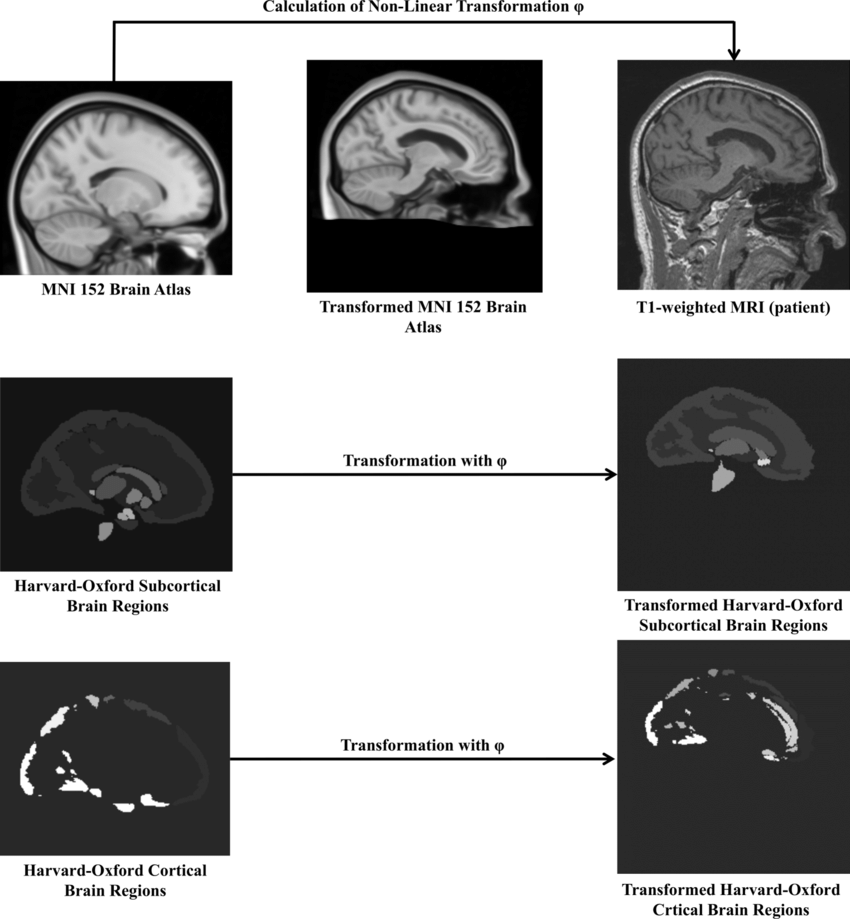

Parkinsonian syndromes encompass a spectrum of neurodegenerative diseases, which can be classified into various subtypes. The differentiation of these subtypes is typically challenging. The aim of this project is to develop image-based classification methods of patients with Parkinson’s disease on diffusion-tensor magnetic resonance imaging (MRI).